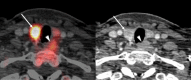

Background: It is well known that primary hyperparathyroidism (PHPT) is one of the most common endocrine disorders. Precise preoperative adenoma localization is essential for increasing PHPT cure rate. Conventional localization techniques include neck ultrasound, 99m-Tc-sestamibi scintigraphy, and computed tomography (CT). However, all of these methods have limitations. 11C-methionine positron emission tomography/computed tomography (PET/CT) combines both anatomical and functional modalities; it may be useful in terms of lowering the imaging procedures number and improving accuracy.

Results: The sensitivity of 11C-methionine PET/CT was 98%, CT, 99m-Tc-sestamibi scintigraphy, and ultrasound showed sensitivity at 75%, 79%, and 67%, respectively. The estimated specificities of 11C-methionine PET/CT, CT, 99m-Tc-sestamibi scintigraphy and ultrasound were 93%, 73%, 75%, and 70%, respectively.

Conclusions: Our study showed that 11C-methionine PET/CT has higher sensitivity and specificity than conventional techniques in a group of 19 patients. 11C-methionine PET/CT may take a place in the imaging of parathyroid adenomas, it may replace CT and 99m-Tc-sestamibi scintigraphy while simultaneously providing information about lesion topography and function.